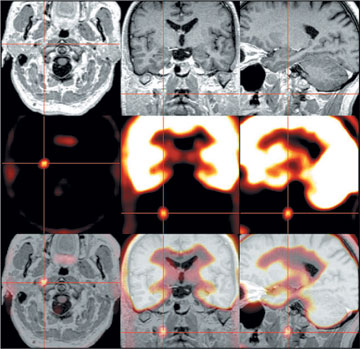

Bei diesem Patienten, der nach überstandenem Schilddrüsenkrebs wieder erhöhte Tumormarker aufwies, konnte erst mit der PET-Aufnahme des Kopf-Hals-Bereiches eine Lymphknotenmetastase aufgespürt werden. Gut zu sehen ist, wie PET-Bilder (Mitte) mit Magnetresonanztomographieaufnahmen (oben) kombiniert werden können (unten), um den Tumor (im Fadenkreuz) noch exakter zu lokalisieren. |